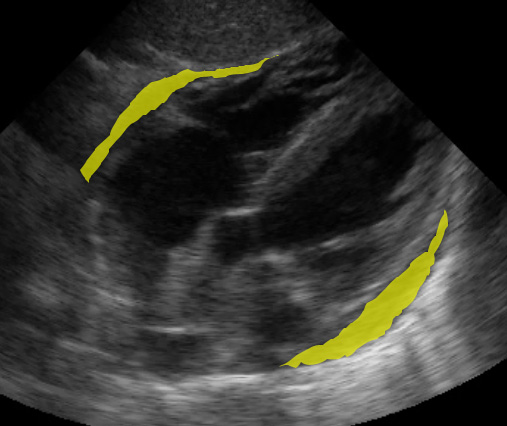

Just like the RUQ, fluid can appear in the splenorenal recess. HOWEVER, the trickiest part of evaluating the LUQ is that fluid is most likely to be found in the subphrenic space, between the spleen and diaphragm.

(Figure 31/31.1)

In the above picture, the red represents subphrenic fluid and the yellow denotes fluid in the splenorenal space.

(Figure 32/32.1)

In this picture above, note the large amount of fluid in the subphrenic space (yellow) despite the lack of fluid in the splenorenal space. Also note the fluid in the left thorax (red).